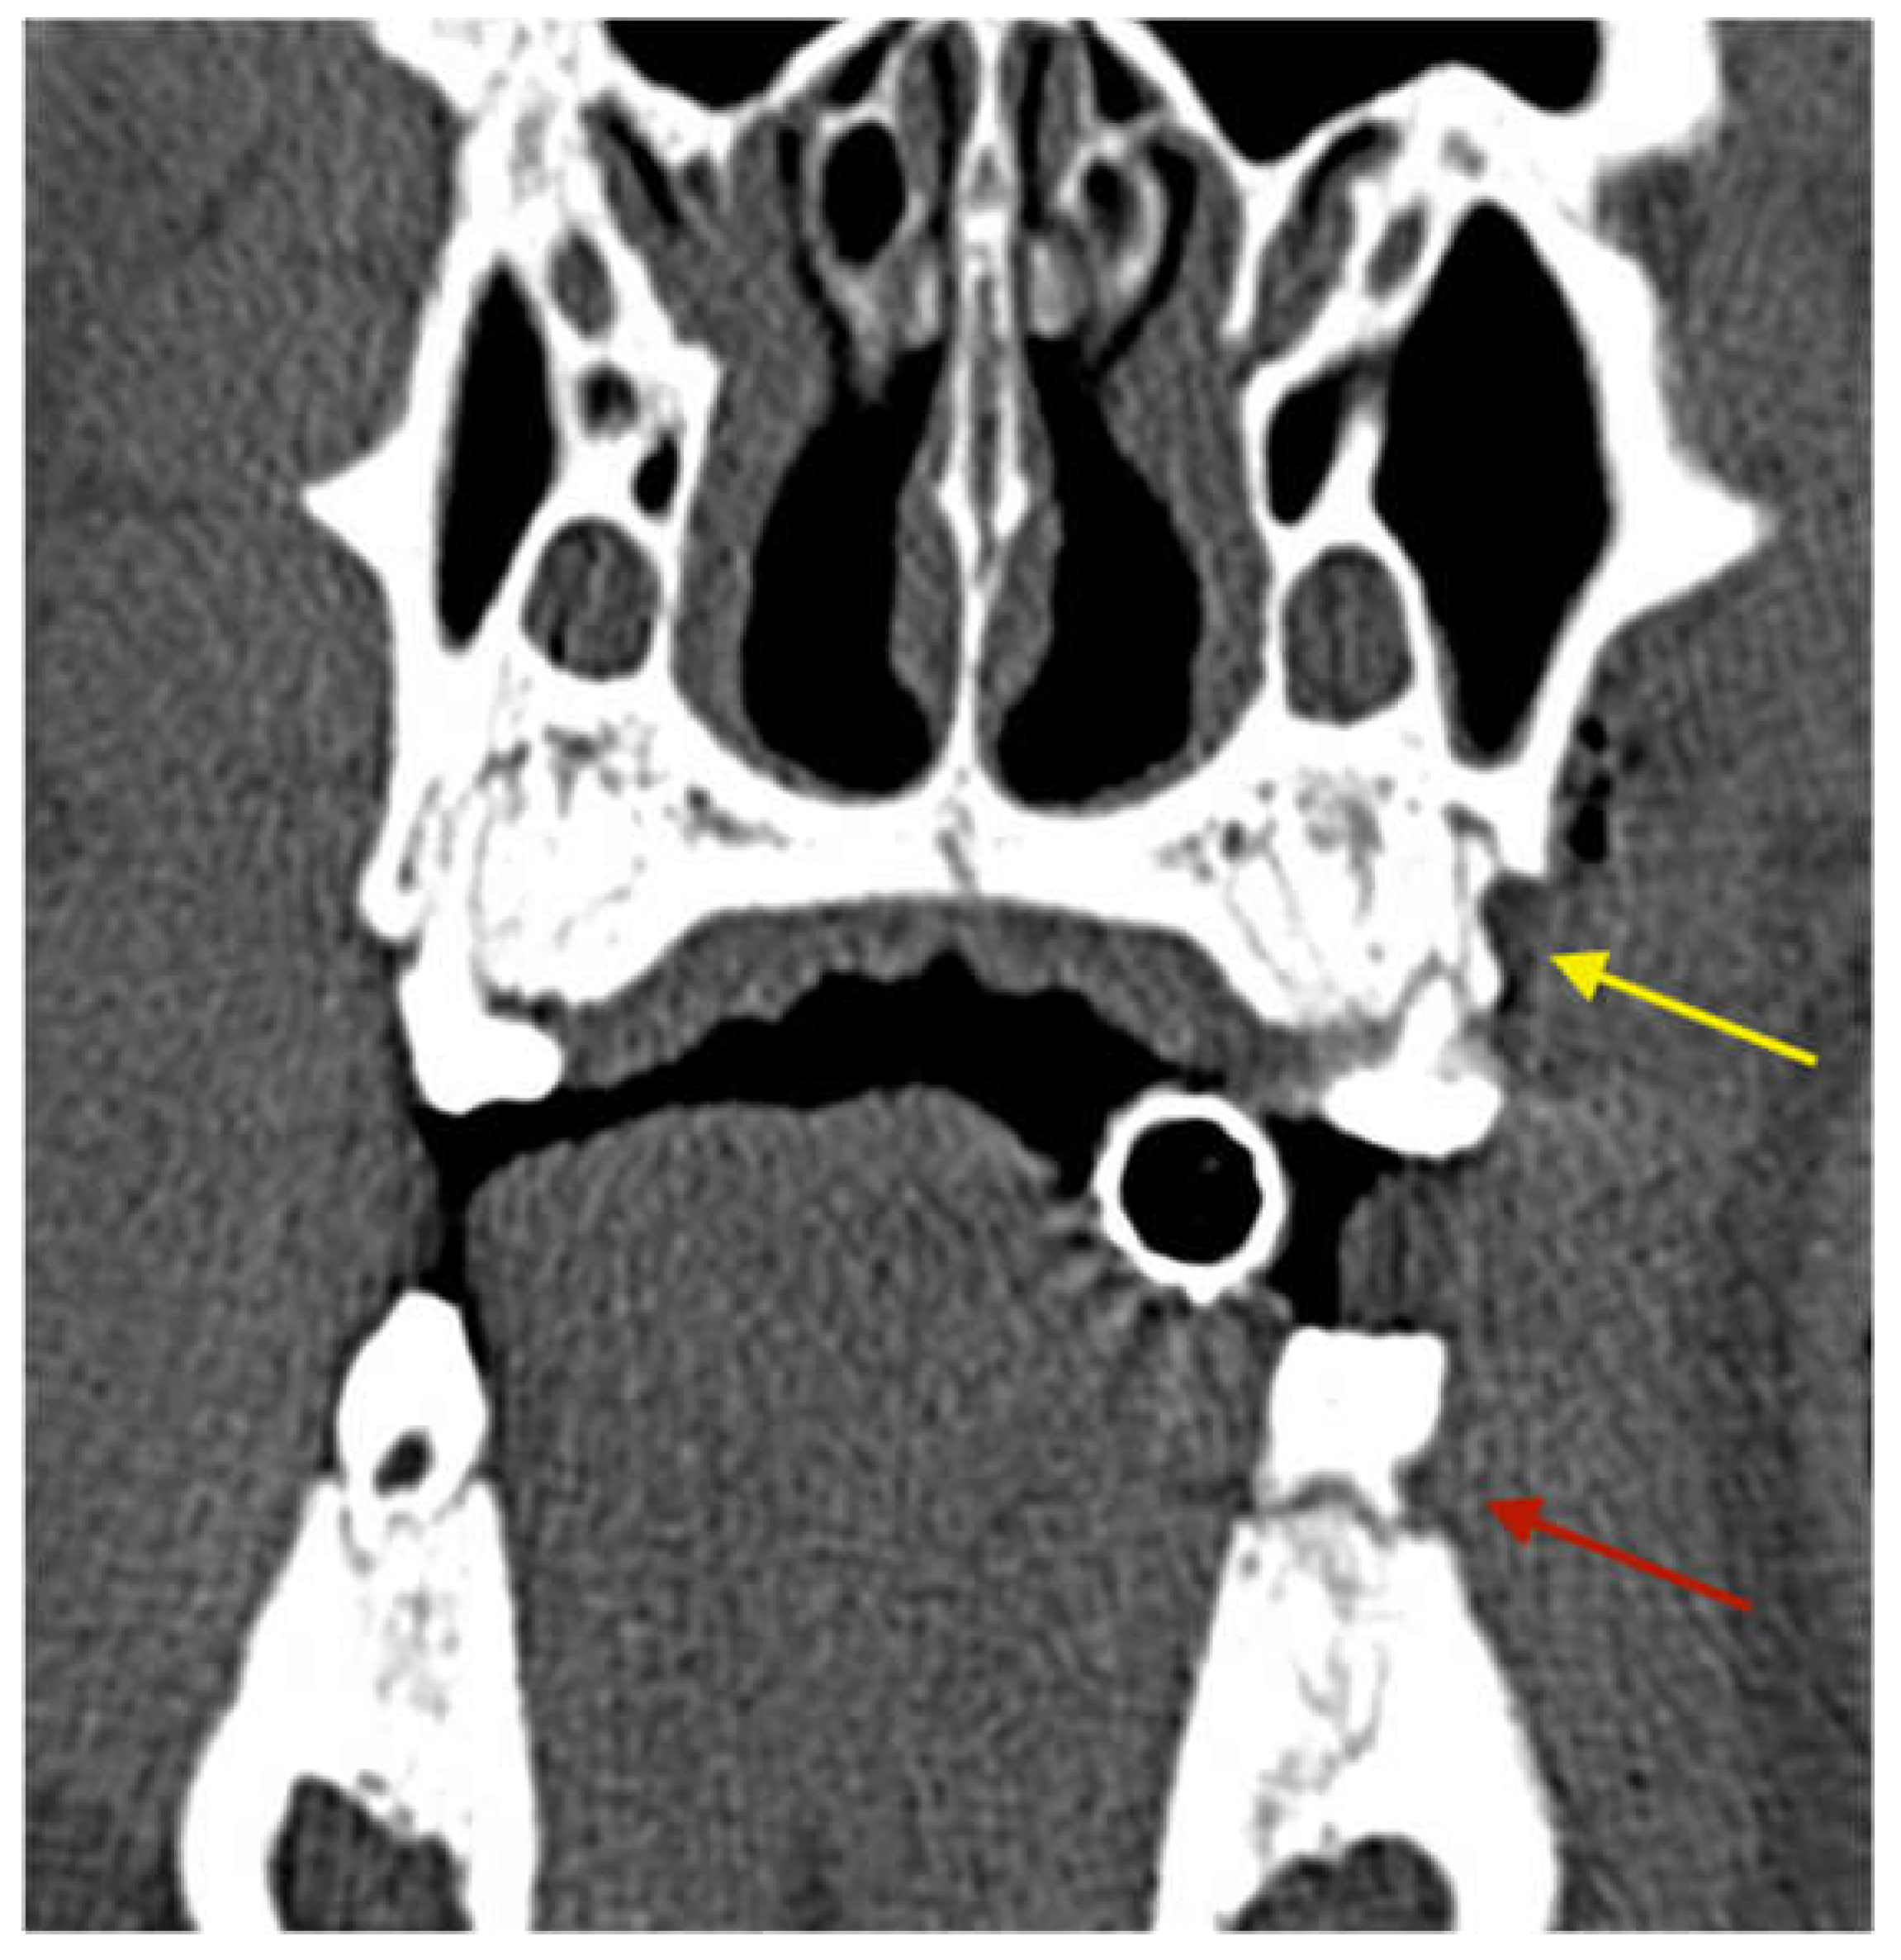

3.2.3. Radiological Evaluation